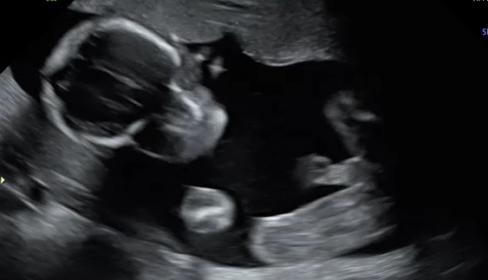

Team Green No Longer ??? 20 week scan

Hi! I recently went to my 20 week scan with the intention of being team green! All went well during the scan and I didn't see any definitive "bits". The pictures the tech sent me didn't seem to give any clues....but then I make the mistake of watching the DVD with live shots. I seems like there is a brief glimpse of boy parts in the shot where the baby is facing forward. It looks like a potty shot, but I haven't seen any with the skull visible, so I am not sure what to think. I'm hoping that I am still team green, but these shots make me think otherwise. Any insight would be greatly appreciated!! I am going crazy trying to figure it out. :shrug:

Attachment 42608Attachment 42609Attachment 42610